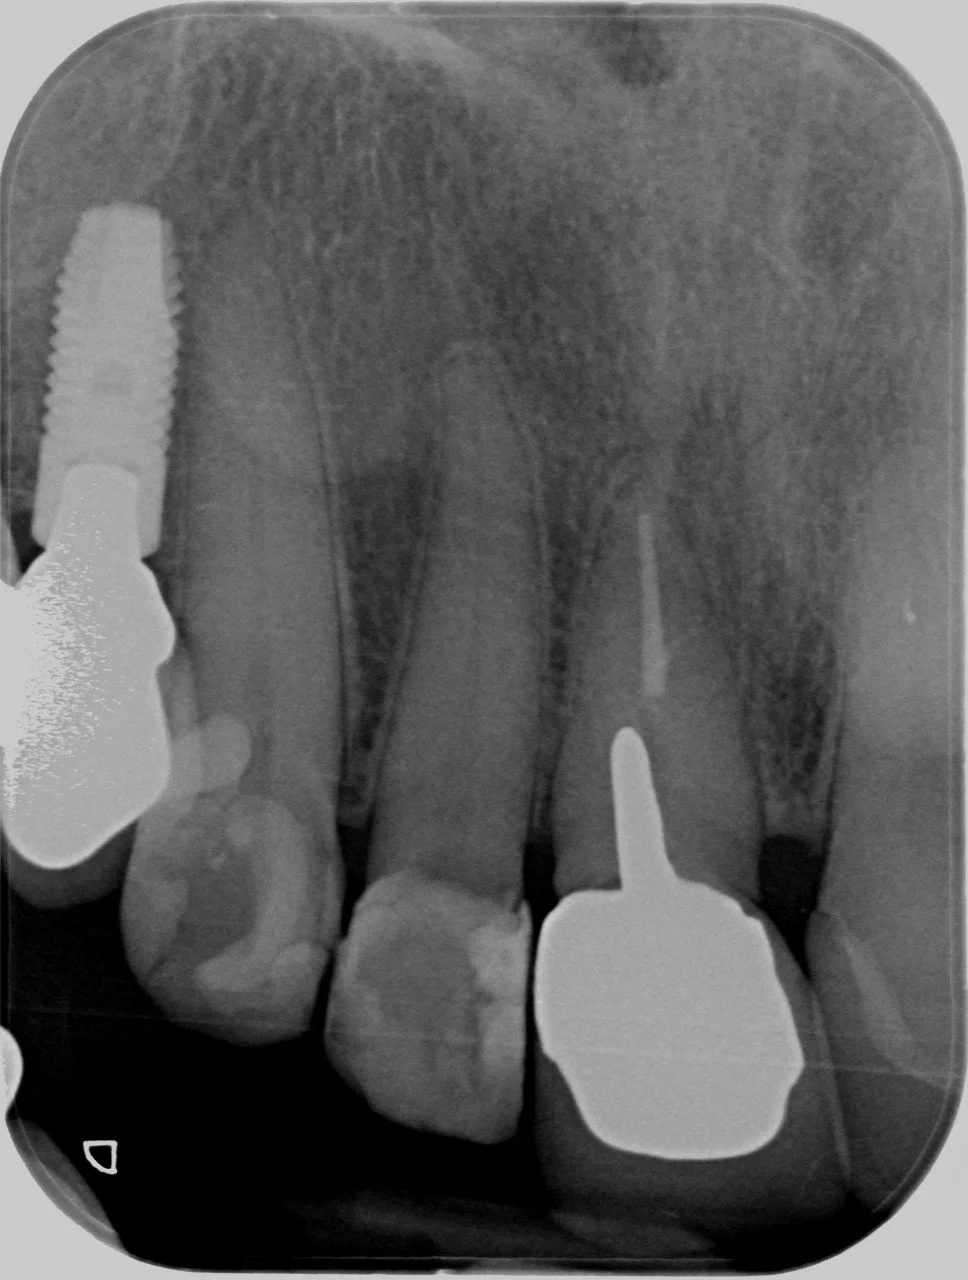

This 60 year old lady had recurring problems with the top right crowned front tooth which was restored with a gold post crown. This post was short and angled and the post crown kept on debonding from the root and the post crown kept falling out of her mouth. Eventually decay ensued and the root cracked as illustrated in the radiograph.

-

The patient was referred to me in 2021 at Lismore and I referred the patient to a Periodontist in Brisbane. He extracted the tooth, placed a temporary partial denture plate to fill the space and subsequently placed a Straumann implant fixture and healing cap

I completed this case at Lismore in 2022 and this radiograph illustrates the completed the screw accessible zirconia implant crown